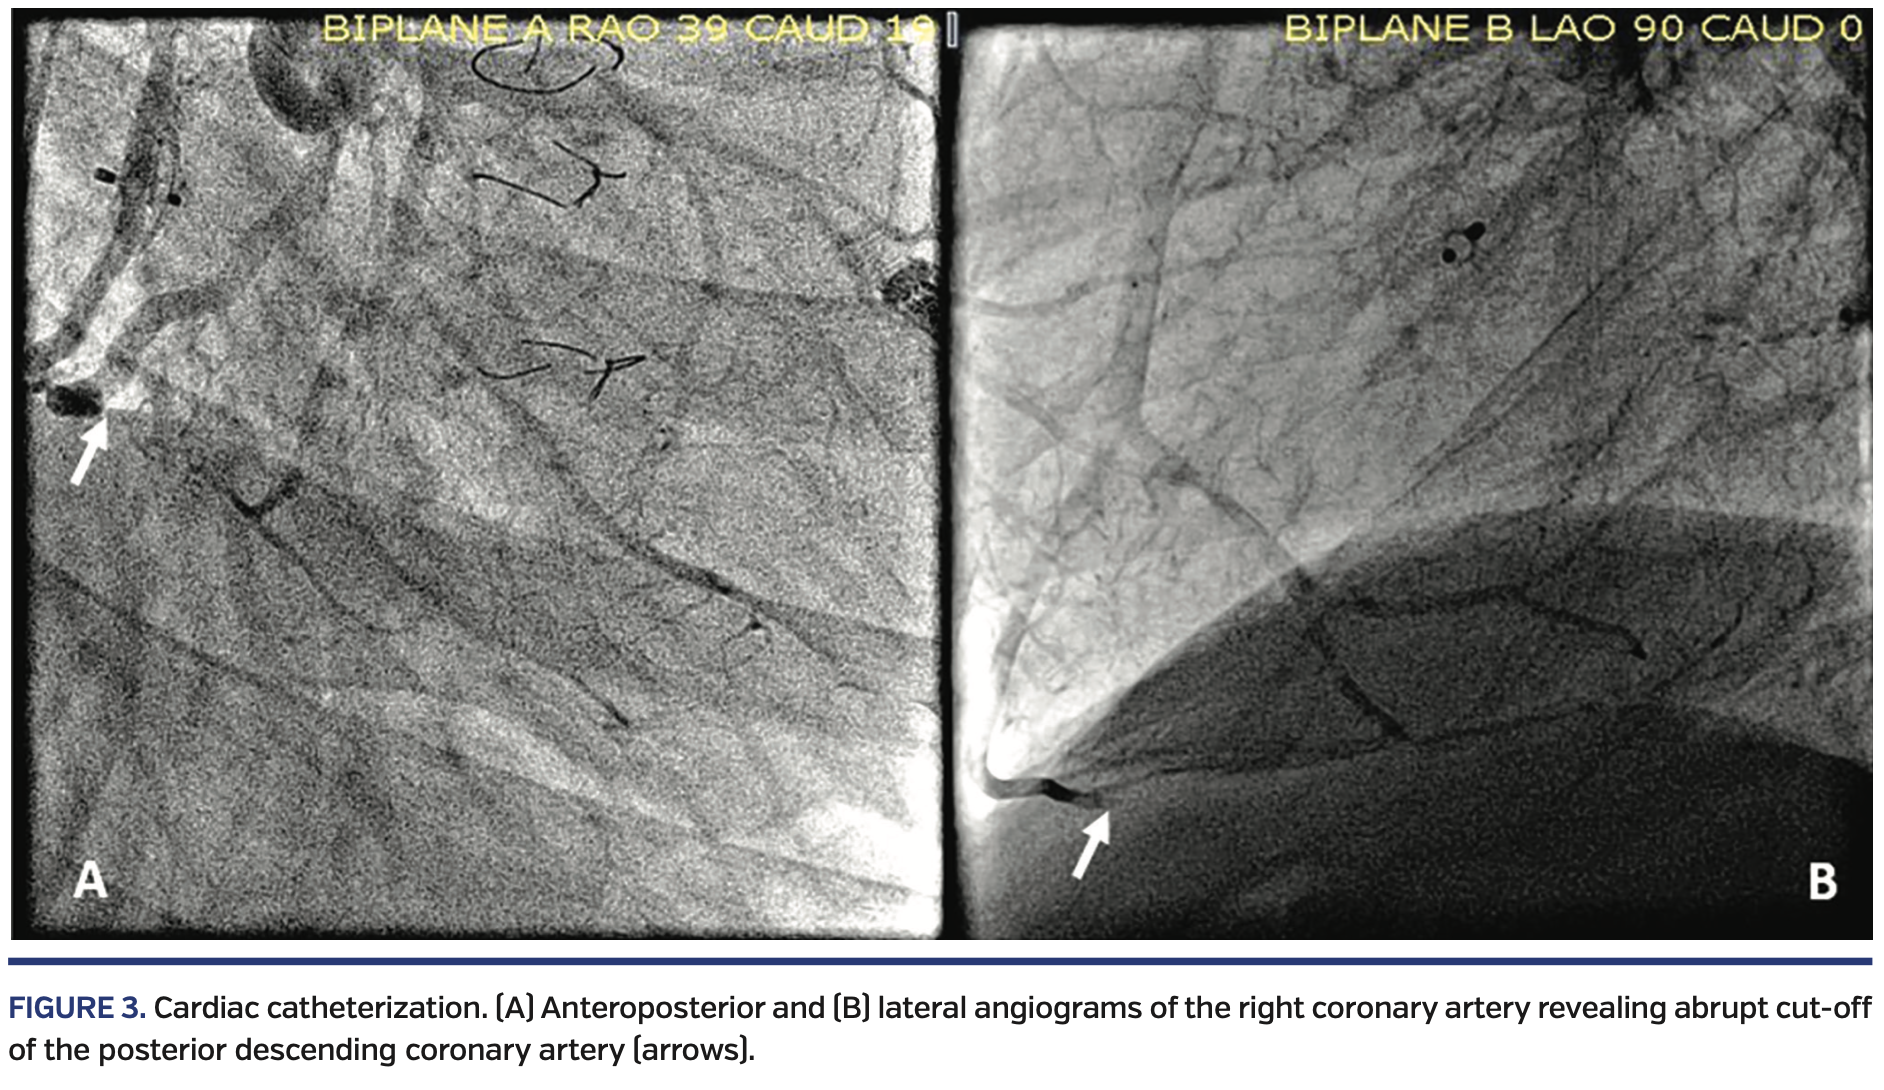

Right lower extremity angiography via antegrade right common femoral artery access showed severe, flow-limiting, 3-vessel tibial disease on the right side, with occluded distal anterior tibial and posterior tibial arteries (Figure 2).

The occlusions in the arteries were crossed with a Fielder FC wire (Asahi-Intecc) and directional atherectomy with a HawkOne S Directional atherectomy system (Medtronic) was performed through the occluded posterior tibial, through the pedal arch, and into the dorsalis pedis artery (Figure 3).